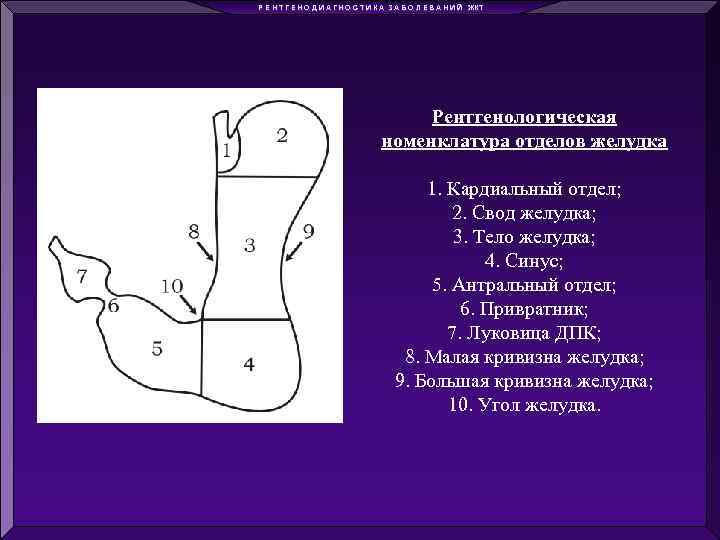

Р Е Н Т Г Е Н О Д И А Г Н О С Т И К А З А Б О Л Е В А Н И Й ЖКТ Рентгенологическая номенклатура отделов желудка 1. Кардиальный отдел; 2. Свод желудка; 3. Тело желудка; 4. Синус; 5. Антральный отдел; 6. Привратник; 7. Луковица ДПК; 8. Малая кривизна желудка; 9. Большая кривизна желудка; 10. Угол желудка.

Р Е Н Т Г Е Н О Д И А Г Н О С Т И К А З А Б О Л Е В А Н И Й ЖКТ Рентгенологическая номенклатура отделов желудка 1. Кардиальный отдел; 2. Свод желудка; 3. Тело желудка; 4. Синус; 5. Антральный отдел; 6. Привратник; 7. Луковица ДПК; 8. Малая кривизна желудка; 9. Большая кривизна желудка; 10. Угол желудка.